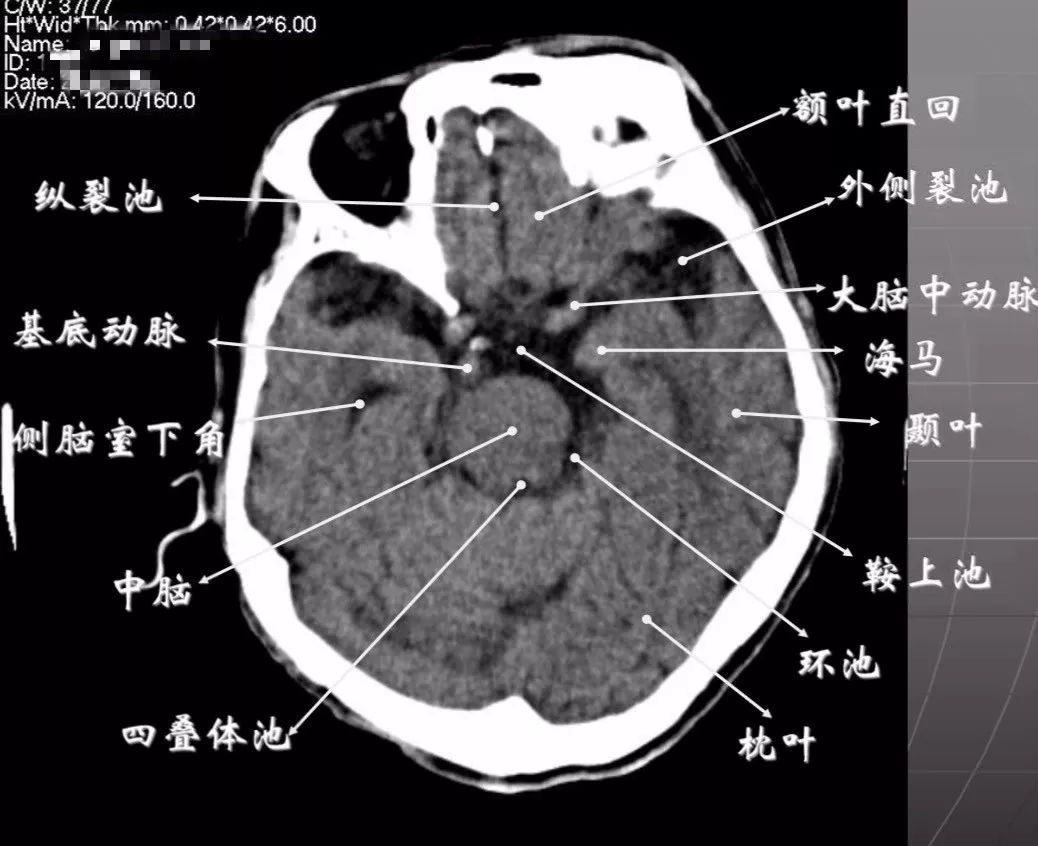

简明又详细的头部ct读片详解

简明又详细的头部ct读片详解收藏